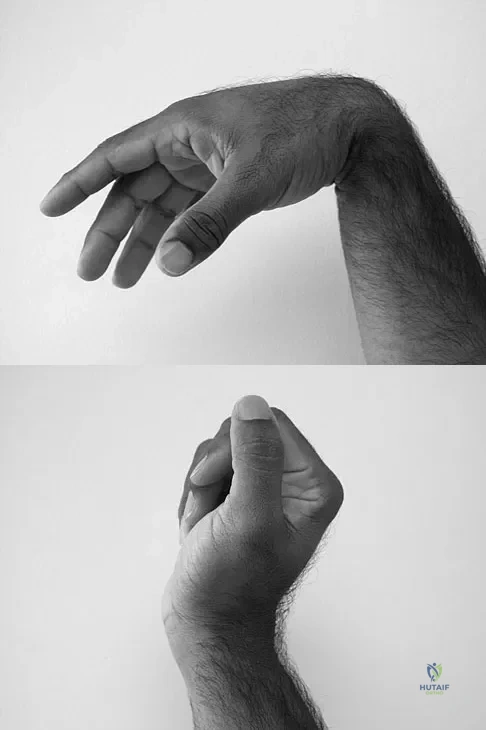

Question 85

A 35-year-old man sustained a 1-inch stab incision in his proximal forearm while trying to use a screwdriver 2 weeks ago. The laceration was routinely closed, and no problems about the incision site were noted. He now reports that he has been unable to straighten his fingers or thumb completely since the injury. Clinical photographs shown in Figures 30a and 30b show the man passively flexing the wrist. What is the most appropriate management?

Explanation